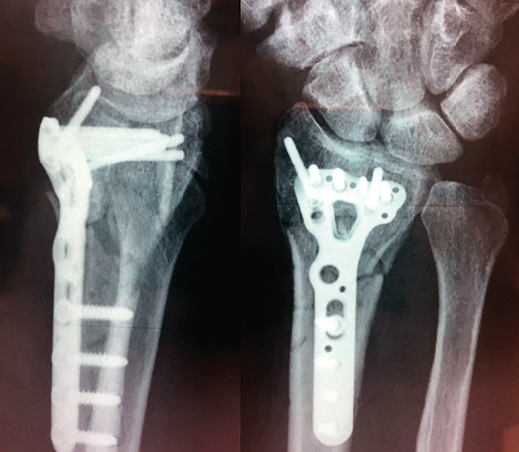

Figura 2. Control posquirúrgico (6 semanas).

Se realiza radiografía simple y tomografía axial computarizada (TAC) (Figura 1). Se llevó a cabo la osteosíntesis con una placa volar Acu-Loc 2® distal ancha larga de Acumed y aporte de hueso de banco liofilizado en el foco metafisario. Se consiguió una reducción correcta (Figura 2). La herida evolucionó sin incidencias y se mantuvo al paciente 3 semanas inmovilizado con férula en U bloqueando la pronosupinación (sugar tongue). Posteriormente, inició una rehabilitación progresiva, con uso de ortesis rígida de descarga y controles clínicos y radiológicos cada 4-5 semanas.